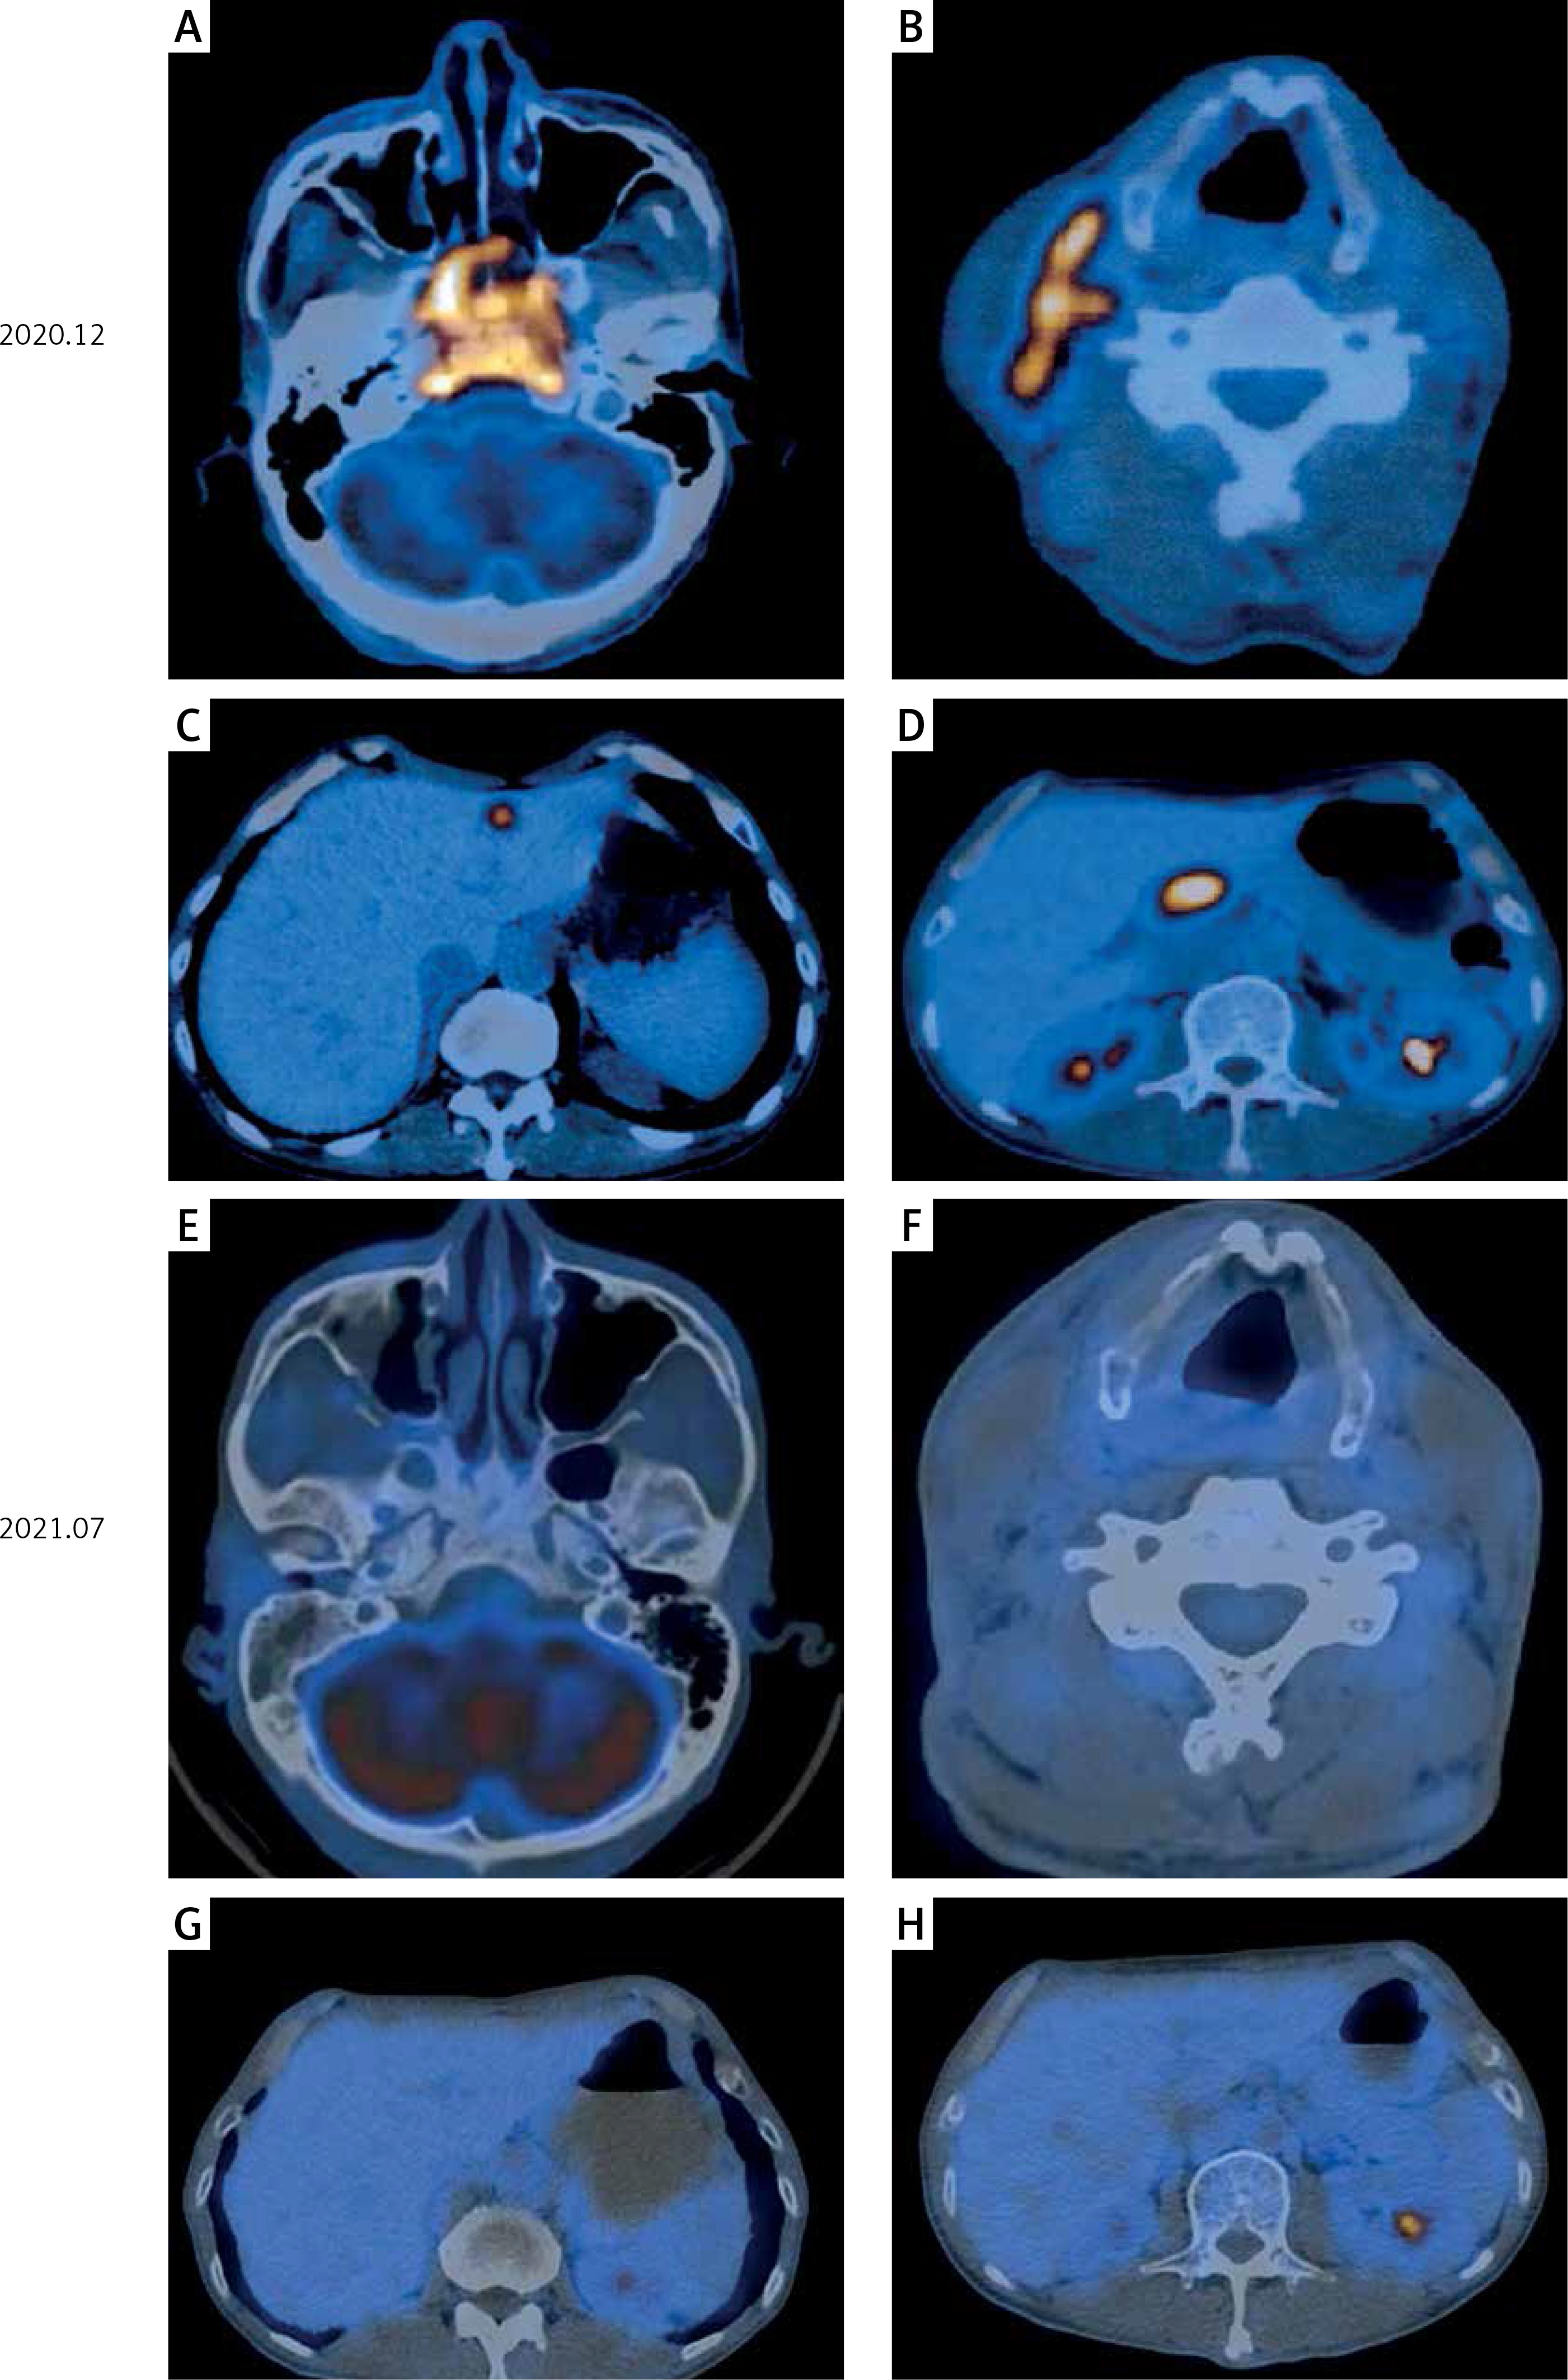

Figure 3

PET-CT showed the primary focus of NPC, lymph node metastasis in the neck, and liver and lymph node metastases in the head of the pancreas. A – Primary lesion before treatment. B – Before treatment, the largest cervical lymph node was 1.9 cm in short diameter. C – Before treatment, the largest liver metastasis was 1.4 cm in short diameter. D – Before treatment, the lymph node metastases in the head of the pancreas were 2.4 cm in short diameter. E–H – After treatment, the primary lesion, lymph node metastasis in the neck, and liver and lymph node metastases in the head of the pancreas completely disappeared